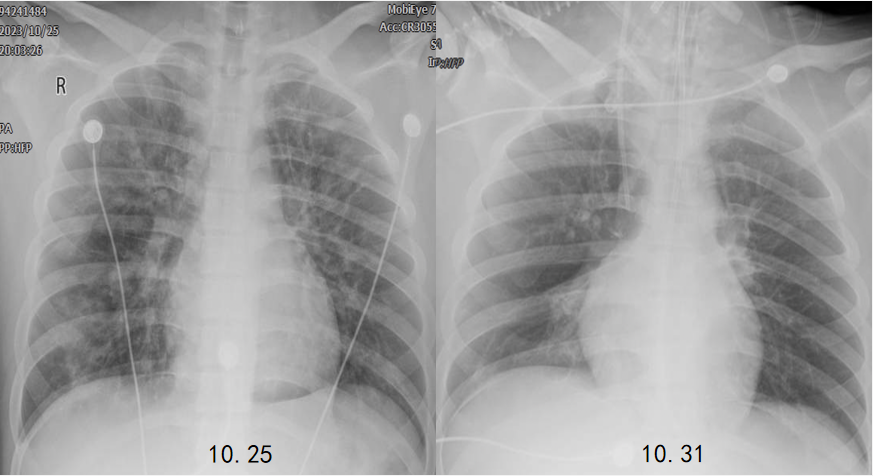

治疗1周后,患者胸部X线片较入院时改善,病变吸收明显(图5)体温也有所下降(图6)

图片

图5  患者胸部X线片